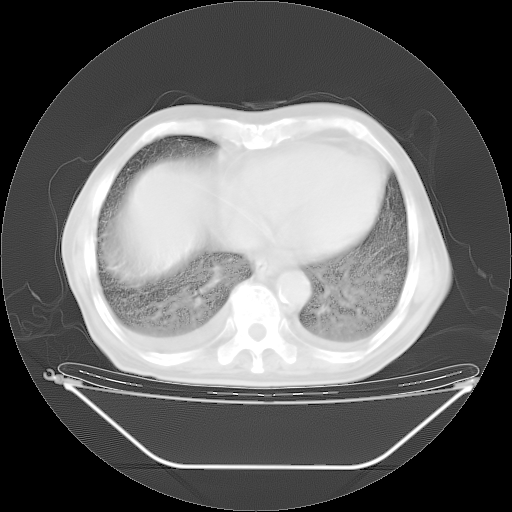

胸腹部CT,诊断意见:左上肺叶钙化灶、左侧胸膜局限性增厚并钙化、胆囊炎。描述部分肺组织呈磨玻璃样改变。